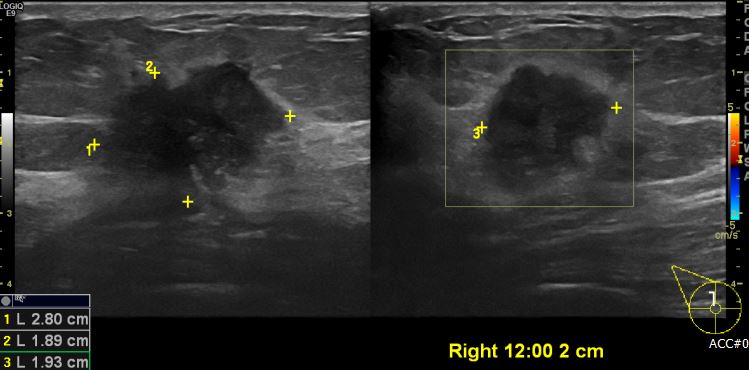

우측 유방에 만져지는 멍울로 내원하신 40대 여성분으로 본원 유방초음파에서  우측

12시 방향에서 2cm 떨어진 거리에 의심스러운 혹 조직검사 시행하여 우측 침윤성 유관암

진단 되었습니다.